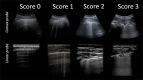

Purpose: Febrile neutropenia and lung infections are common and potential fatal complications of pediatric cancer patients during chemotherapy. Lung ultrasound (LUS) has a good accuracy in the diagnosis of pneumonia in childhood, but there is no data concerning its use in the diagnosis and follow-up of pulmonary infection in children with cancer. The goal of this pilot study is to verify the feasibility of lung ultrasonography for the diagnosis and follow up of pneumonia in children and adolescents with cancer.

Material and methods: This is a prospective observational case-control monocentric study conducted in the Pediatric Hematology and Oncology Department of University Hospital of Catania in patients aged < 18 years with cancer. Attending Physician used ultrasonography to detect pneumonia in cancer children with fever. As control group, cancer patients with no infection suspicion were also tested. LUS results were compared to chest X-ray (CXR) and/or chest CT scan, when these imaging techniques were performed, according to clinical indication.

Results: Thirty-eight patients were studied. All underwent LUS, 16 underwent CXR, 3 chest CT. Statistical analysis showed LUS specificity of 93% (95% CI 84-100%), and sensitivity of 100%; CXR, instead, showed a specificity of 83% (95% CI 62-100%) and a sensitivity of 50% (95% CI 1-99%).

Conclusion: This study shows for the first time that LUS allows physicians to diagnose pneumonia in children and young adults with cancer, with high specificity and sensitivity.